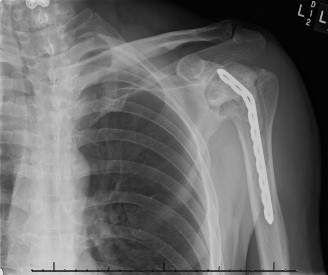

The stabilization procedure for anterior dislocations could involve: capsulolabral repair, disimpaction of the humeral head and bone grafting, size-matched allograft replacement when the remaining cartilage is healthy, or infraspinatus transfer with or without the greater tuberosity (to fill the humeral head defect) using a dual anterior and posterior approach. Similar options exist for posterior dislocations although the transfer would involve a subscapularis/lesser tuberosity transfer, which can be done entirely from an anterior approach. Additional Questions A 27-year-old banker with a seizure disorder presents to your clinic with shoulder pain and stiffness for 1.5 months since his last seizure. His X-ray is shown below (Fig. 2–46).

Figure 2–46

The correct answer is (C). The image demonstrates a chronically dislocated posterior glenohumeral dislocation. At 1.5 months, a dislocation closed reduction is unlikely to be successful. Each of the answer choices shows an acceptable treatment option depending on the stability of the reduction and the size of the humeral head impaction fracture except for Answer C, open reduction and greater tuberosity transfer. This would be used for posterior defects that would be seen with anterior dislocations.